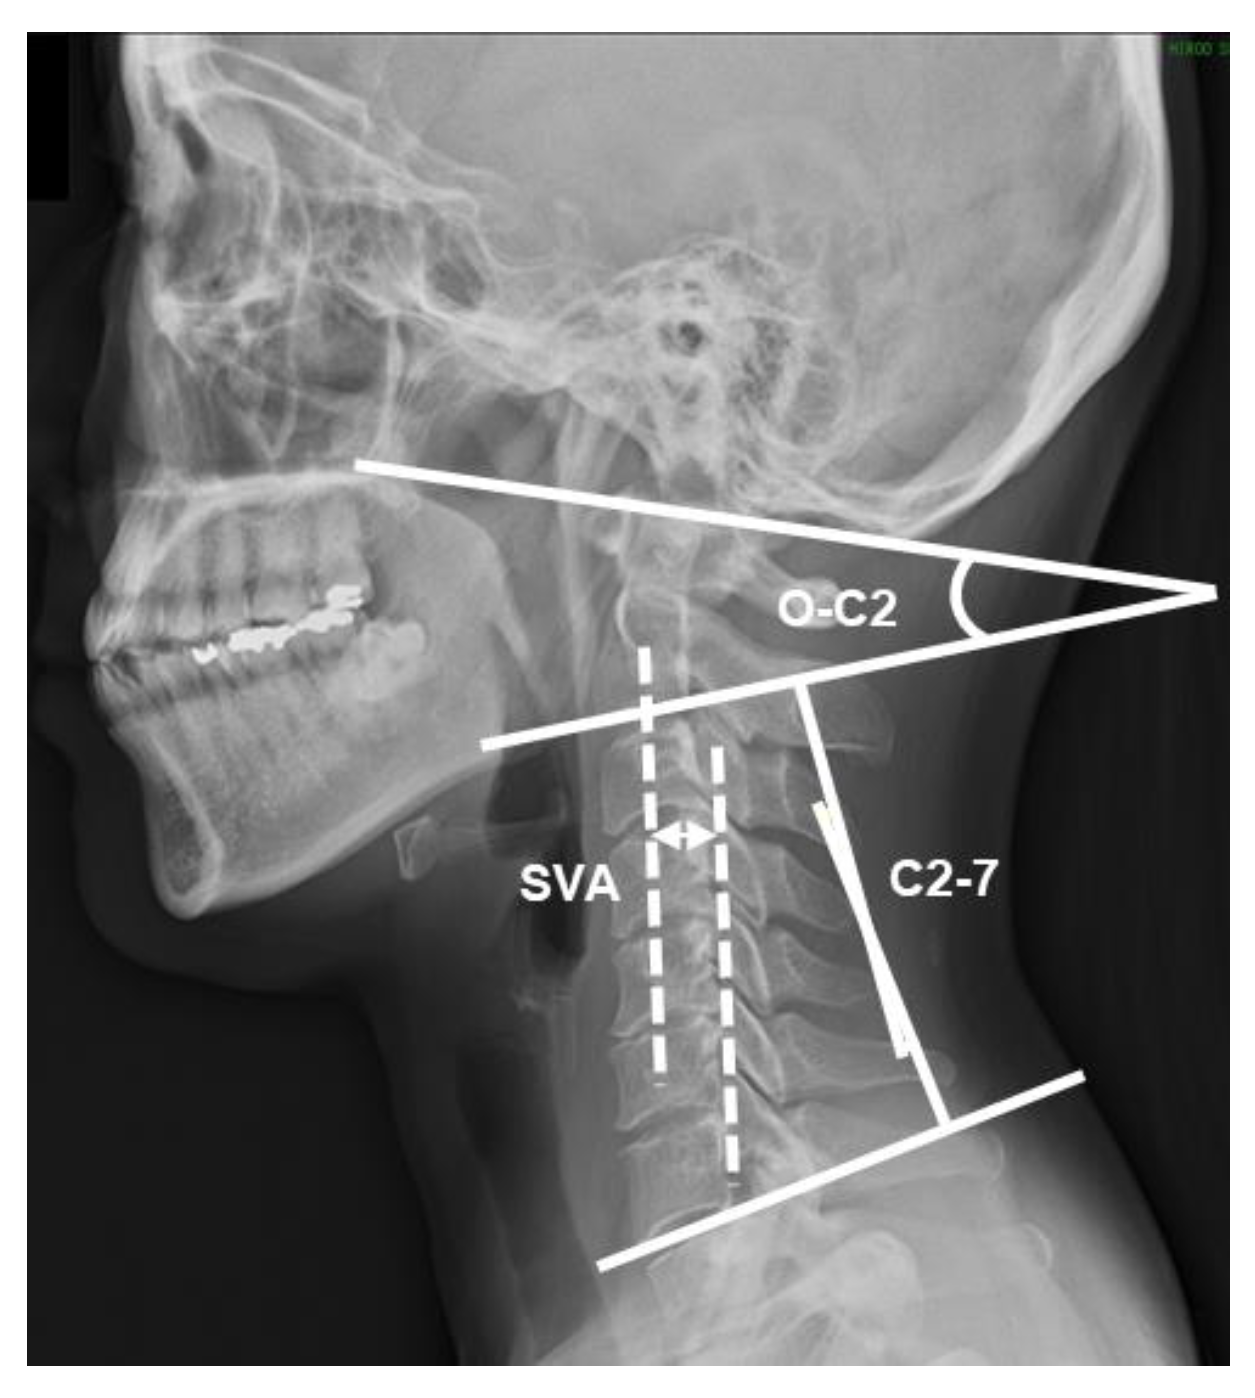

2.3. Radiographic Measurements

| SVA (mm) | 2.3 | 1.9 | 1.3/4.5 | 2.1 | 0.7 | 2.5 | 1.4 | 0.06 |

| C2-7 (degrees) | 6.3 | 17.6 | −12.1/20.1 | 6.3 | 18.1 | 8.3 | 12.3 | 0.57 |

| O-C2 (degrees) | 16.6 | 7.7 | 4.1/30.3 | 14.3 | 8.2 | 19.8 | 4.6 | 0.13 |